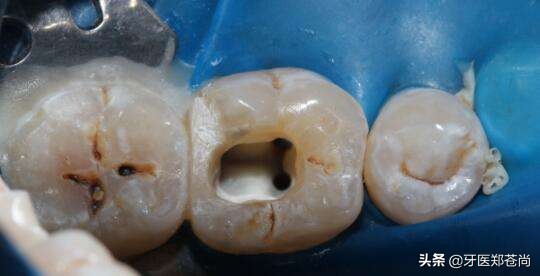

修复的是治疗后的患牙牙洞,如果不修复,一方面外面的细菌、脏东西等还会再次进入到牙齿内部,另一方面,治疗后的牙齿比平时的脆弱,如果不修复保护起来,在使用中容易发生崩脆、劈裂。

根管治疗和修复可以说是一体的,患牙是必须要做修复。

1.根管治疗后进行牙冠修复是为了保护患牙,保证其安全和正常使用功能。